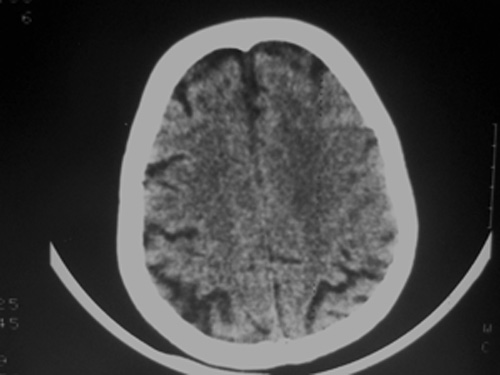

患者63岁,男。左侧肢体活动不灵一小时来诊。bp:175/75;家人否定有脑出血、脑梗死及其他病史。有嗜酒习惯。ct:右侧外囊区见不规则高密度影,边清,肯定是出血。可其周围低密度,边清,ct值与脑脊液相近,不像是水肿影,好似一软化灶形成。这种混合型病灶少见,请老师给予指导一下。

双侧额岛叶萎缩,病者有嗜酒习惯,考虑可能由酒精中毒引起的脑软化灶,合并脑出血,右基底节区亦有软化灶